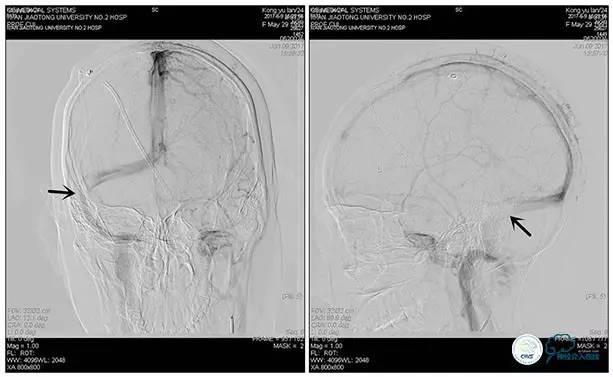

术后造影

术毕远近端压力差为:0